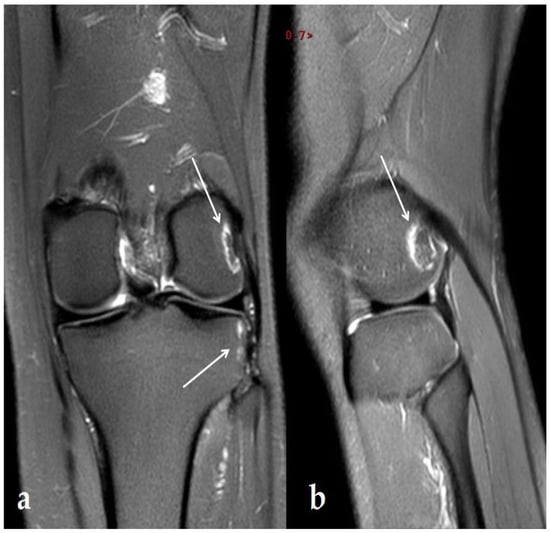

2. Case Report

3.1. Knee Lesions Encountered

3.1.2. Osteonecrosis Lesions of the Knee